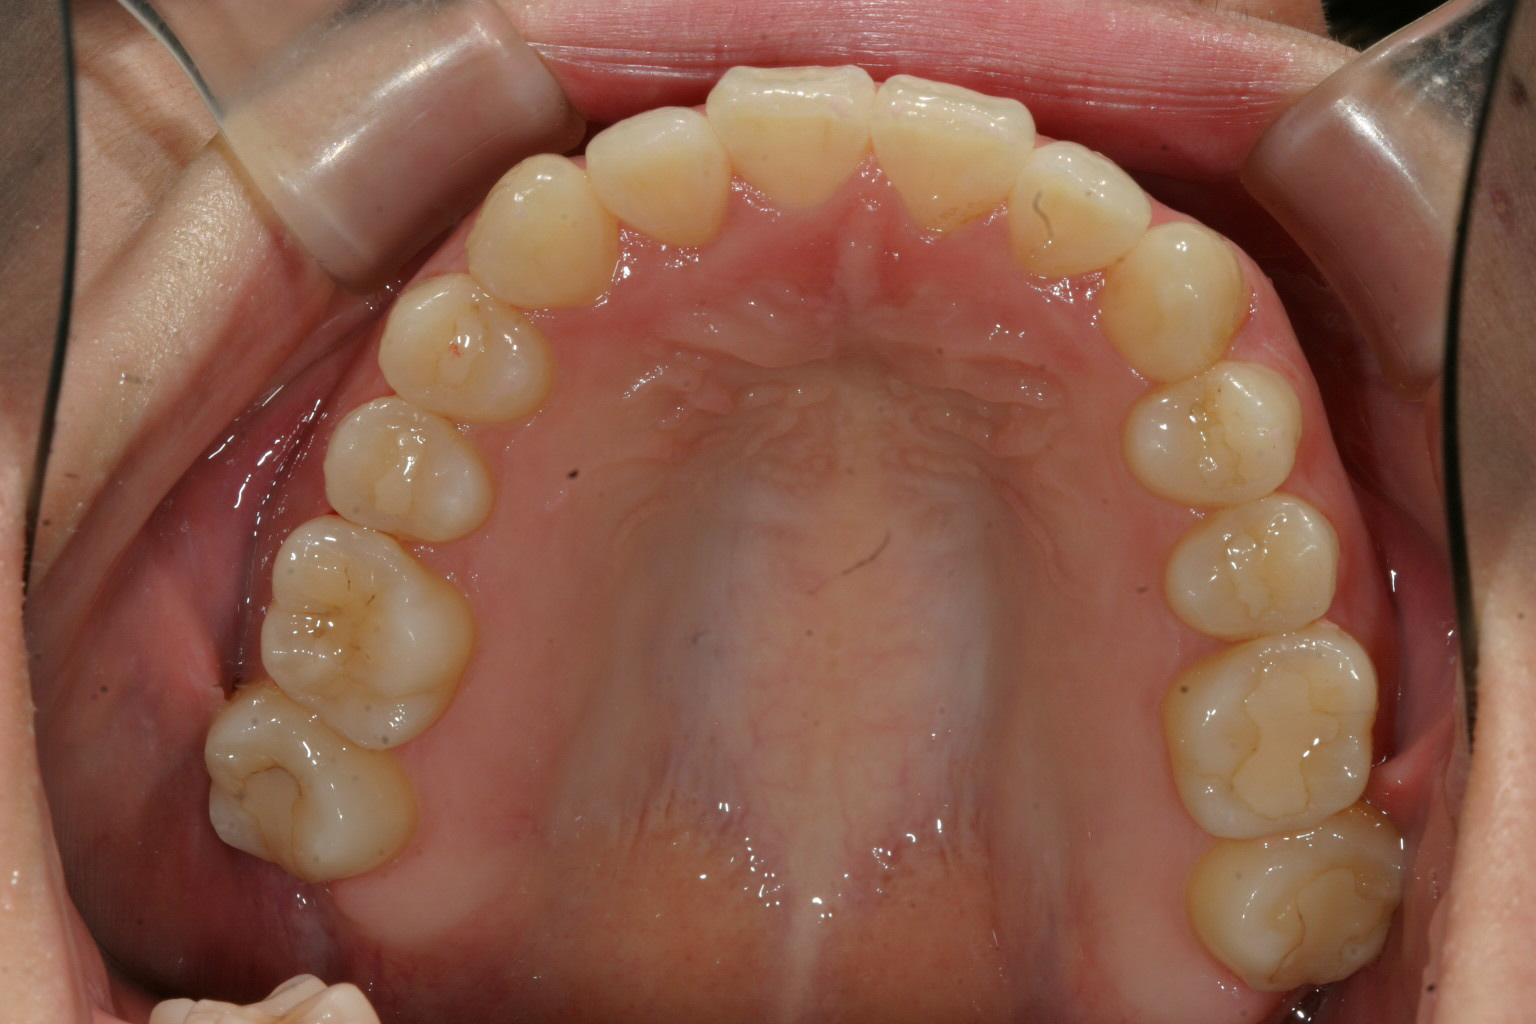

綺麗に改善してます。

綺麗な被蓋関係が出来ました。